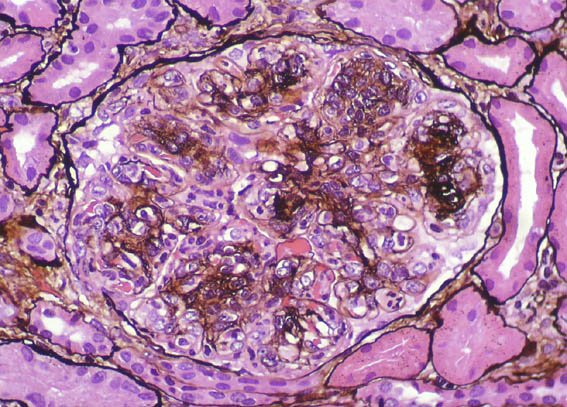

Figure 3.

Masson's

trichrome stain,

X400.